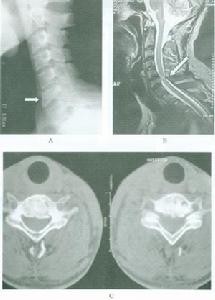

普通X線檢查中,頸椎側位片和矢狀面的斷層對Ⅰ型骨折的診斷非常有用。側位片可顯示骨折線通過樞椎椎體背側,椎體的前方大部分和寰椎一道向前移位,並伴屈曲或伸展的成角畸形,而其椎體後、下部位仍在原處,位於C3椎體上方的正常位置,斷層以片可清楚顯示骨折線及骨折塊移位的情況。開口位片和冠狀面的斷層片對Ⅱ型骨折的診斷非常有價值,可顯示樞椎側塊塌陷、寰椎側塊進入樞椎上關節面。

CT尤其是CT三維重建對了解骨折的全面信息非常重要。

MRI對軟組織的良好解析度使其在脊髓損傷中使用廣泛;同樣,在樞椎椎體骨折患者中,MRI可清楚顯示脊髓損傷和受壓的情況。